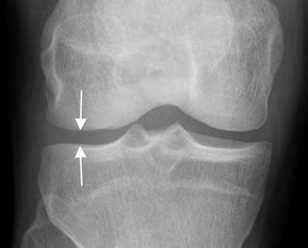

Iniciar el estudio con Rx simple. Con esta modalidad se puede valorar el espacio articular, el grado de destrucción ósea o reacción perióstica, lesiones traumáticas, calcificaciones anormales, etc.

El cartílago y la cavidad articular son radiotransparentes y forman el espacio articular radiológico. (Fig 3).

El derrame articular y laxitud ligamentaria, producen distensión de la cápsula y aumento del espacio. Por el contrario el daño del cartílago, ocasiona disminución del espacio. (3).

Fig 3. Espacio articular normal.

Rx AP. Espacio articular, entre las estructuras óseas.